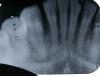

Максим А Опубликовано 12 марта, 2010 Автор Поделиться Опубликовано 12 марта, 2010 Спасибо за совет. Снял, как смог. В домашних условиях только так. Возможно что-то будет понятно из этих снимков. Очень жду ваших мнений... (скрестил пальцы). Под удар попали зубы - 2,3,4, если считать слева. Подозрения (думаю, вы и сами увидите, насчет второго). Ссылка на комментарий

Astronaft Опубликовано 12 марта, 2010 Поделиться Опубликовано 12 марта, 2010 Возможно , но это клык.http://dental-files.ucoz.ru/illustration/help.jpg Ссылка на комментарий

pawa Опубликовано 12 марта, 2010 Поделиться Опубликовано 12 марта, 2010 А по моему проблема тут Ссылка на комментарий

Bier Опубликовано 12 марта, 2010 Поделиться Опубликовано 12 марта, 2010 по клыку согласен, похоже там есть трещина.Второй снимок - я не уверен. Ссылка на комментарий

pawa Опубликовано 12 марта, 2010 Поделиться Опубликовано 12 марта, 2010 А мне кажется, что на клыке просто царапина на снимке так ноложилась, они там и в других местах есть если приглядеться. Не похоже, чтоб мощный клык треснул в двух местах. Ссылка на комментарий

Максим А Опубликовано 13 марта, 2010 Автор Поделиться Опубликовано 13 марта, 2010 Ну, ребята, вы подкинули мне головняк... С клыком у меня нет и не было проблем. Удар туда не прилетал.pawa показал именно то место, в отношении которого у моего стоматолога возникли сомнения.И я хотел бы услышать ваше мнение именно по обведенной красным части.Там перелом, трещина или что-то еще?Или вдруг это дефект рентген-аппарата, качество схемки и т.п. Прошла неделя с момента травмы. Сейчас зубы в покое абсолютно не болят, шататься стали меньше, при накусывании боль стала меньше. Ссылка на комментарий